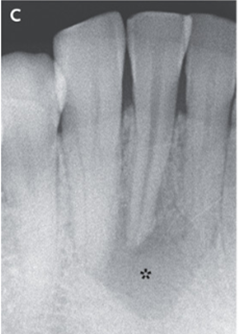

歯科由来の病変の可能性を考慮し歯科受診、X-p施行された。

X-p所見としては色調変化を認めた歯の周囲の根尖周囲の希薄化と骨融解像が認められた。